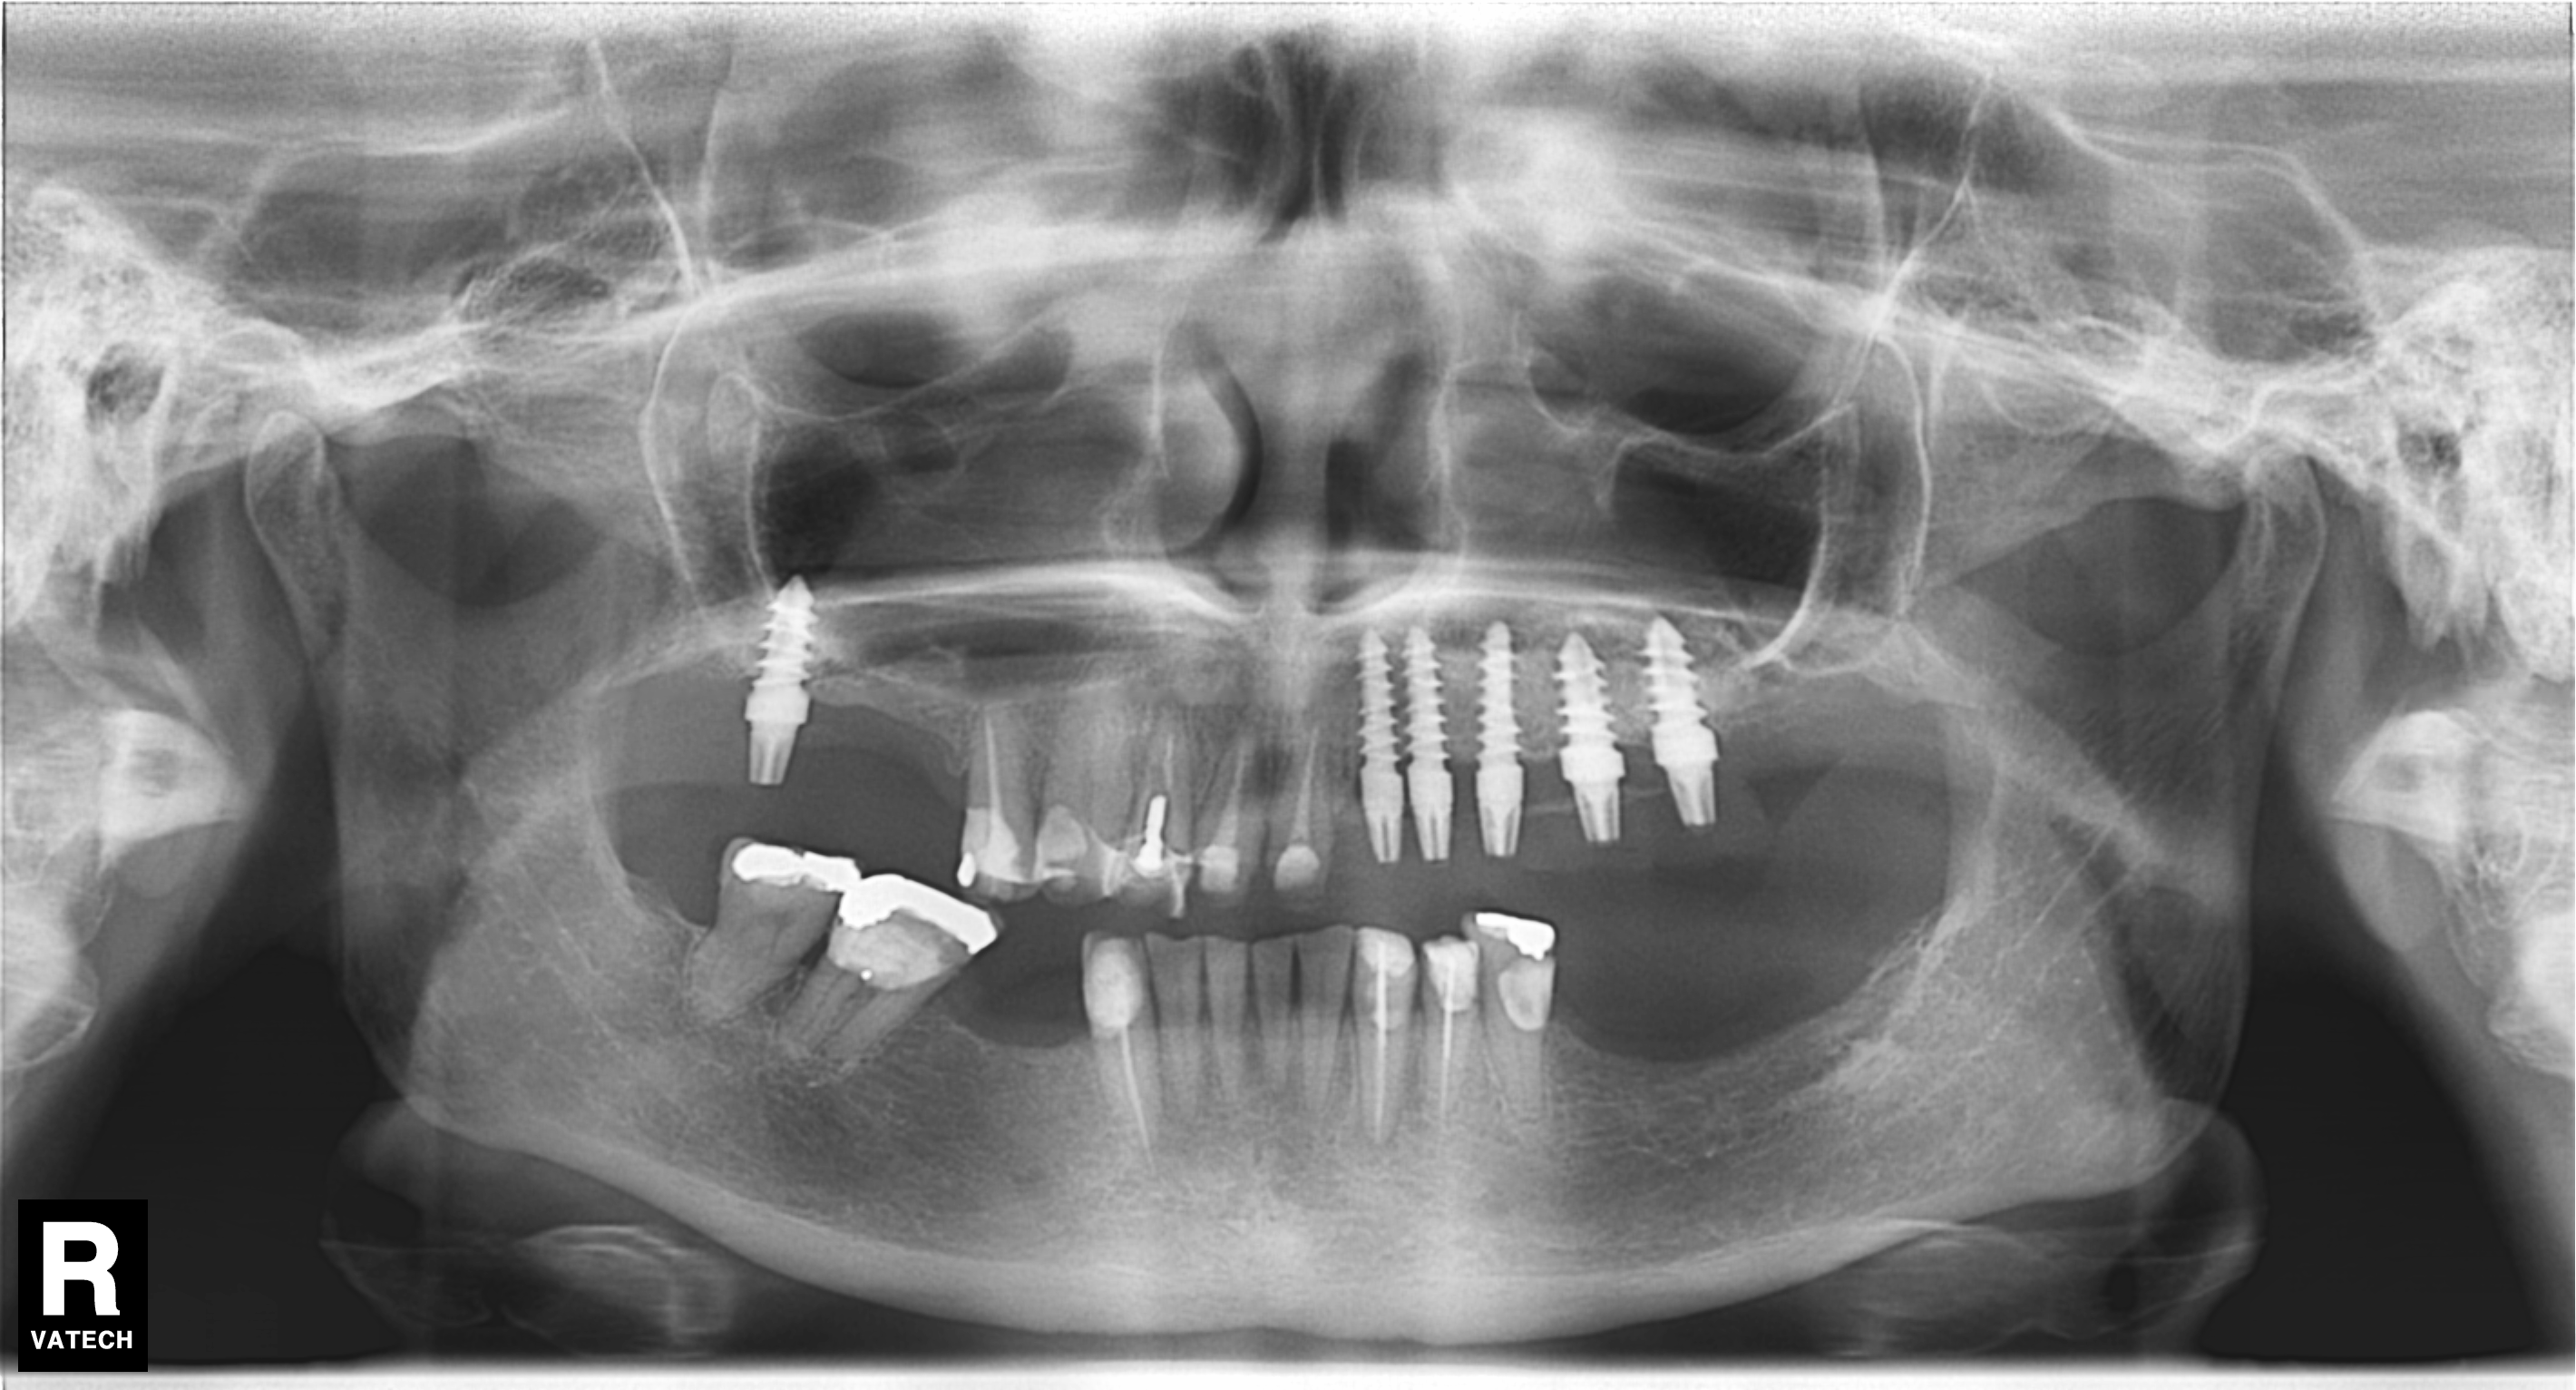

Hola buenos días adjunto Rx Panorámica para ver si me pueden decir que marca de implantes es, a la paciente le dijeron que eran implantes españoles, pero eso no es [...]